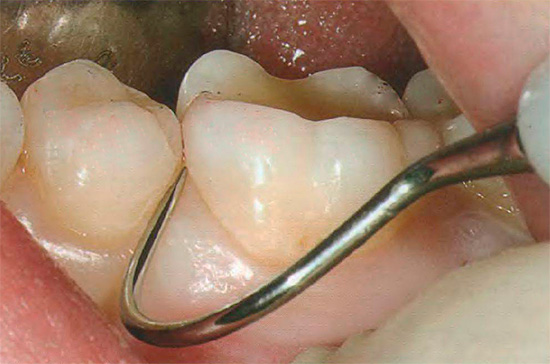

- Suono della superficie della radice. In questo caso, viene utilizzata solo una sonda appuntita, che consente di distinguere i tessuti sani dalle carie colpite dalla caratteristica rugosità superficiale.